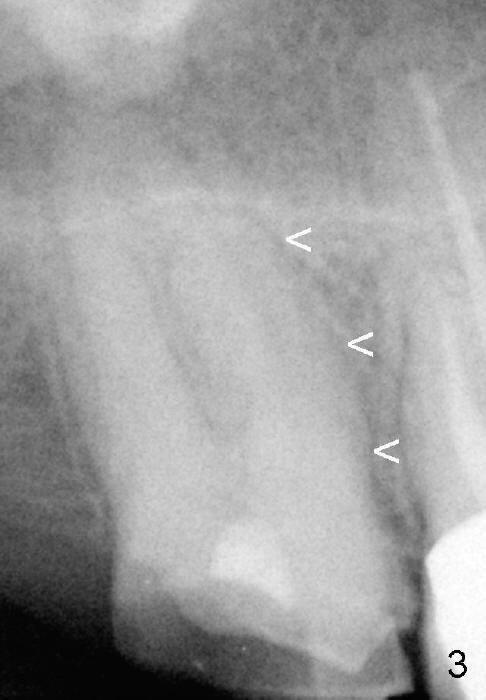

Fig.8 (immediately postop, 7x17 mm implant) <: mesial lamina dura of the shrinking mesiobuccal socket.